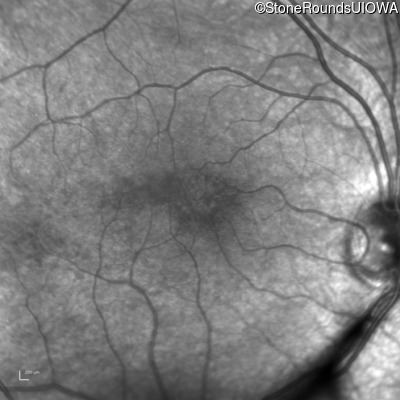

Age at visit: 7 years

OD OS

Age at visit: 9 years

Age at visit: 11 years